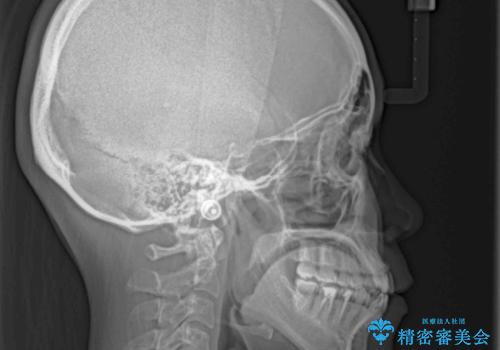

- 上下の前歯の反対咬合を気にして来院された患者様です。

インビザラインを用い、下顎はIPR(歯と歯の間を削る)と歯列全体を後方に移動させ、上顎は前歯を持ち上げることで、反対咬合を改善していくこととしました。